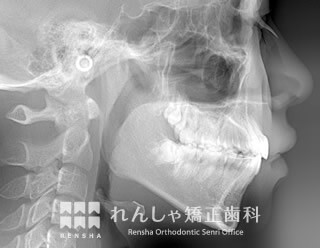

上顎前突(18歳 治療期間:2年10か月)

上前歯をできるだけ内側に移動させたい場合は、抜歯するだけでなく上奥歯を後方へ移動します。

上前歯を大きく後方に移動することができれば、口元を大きく変化させることができます。

| 主訴 | 上前歯の前突 |

|---|---|

| 診断名 | Angle Class II 上顎前突 |

| 初診時年齢 | 16歳2か月 |

| 装置名 | マルチブラケット装置 |

| 抜歯非抜歯 | 上下顎左右第一小臼歯の抜歯(合計4本) |

| 治療期間 | 2年10か月 |

| 費用の目安 | 約88万円+消費税(検査料金、都度の処置費用等も合わせた総額) |

| リスク副作用 | 歯の移動に伴う軽微な歯根吸収、歯槽骨吸収、歯肉退縮(いずれも本症例ではほぼ無し)、矯正器具装着中のカリエスリスク増大(本症例ではカリエス発生無し) |